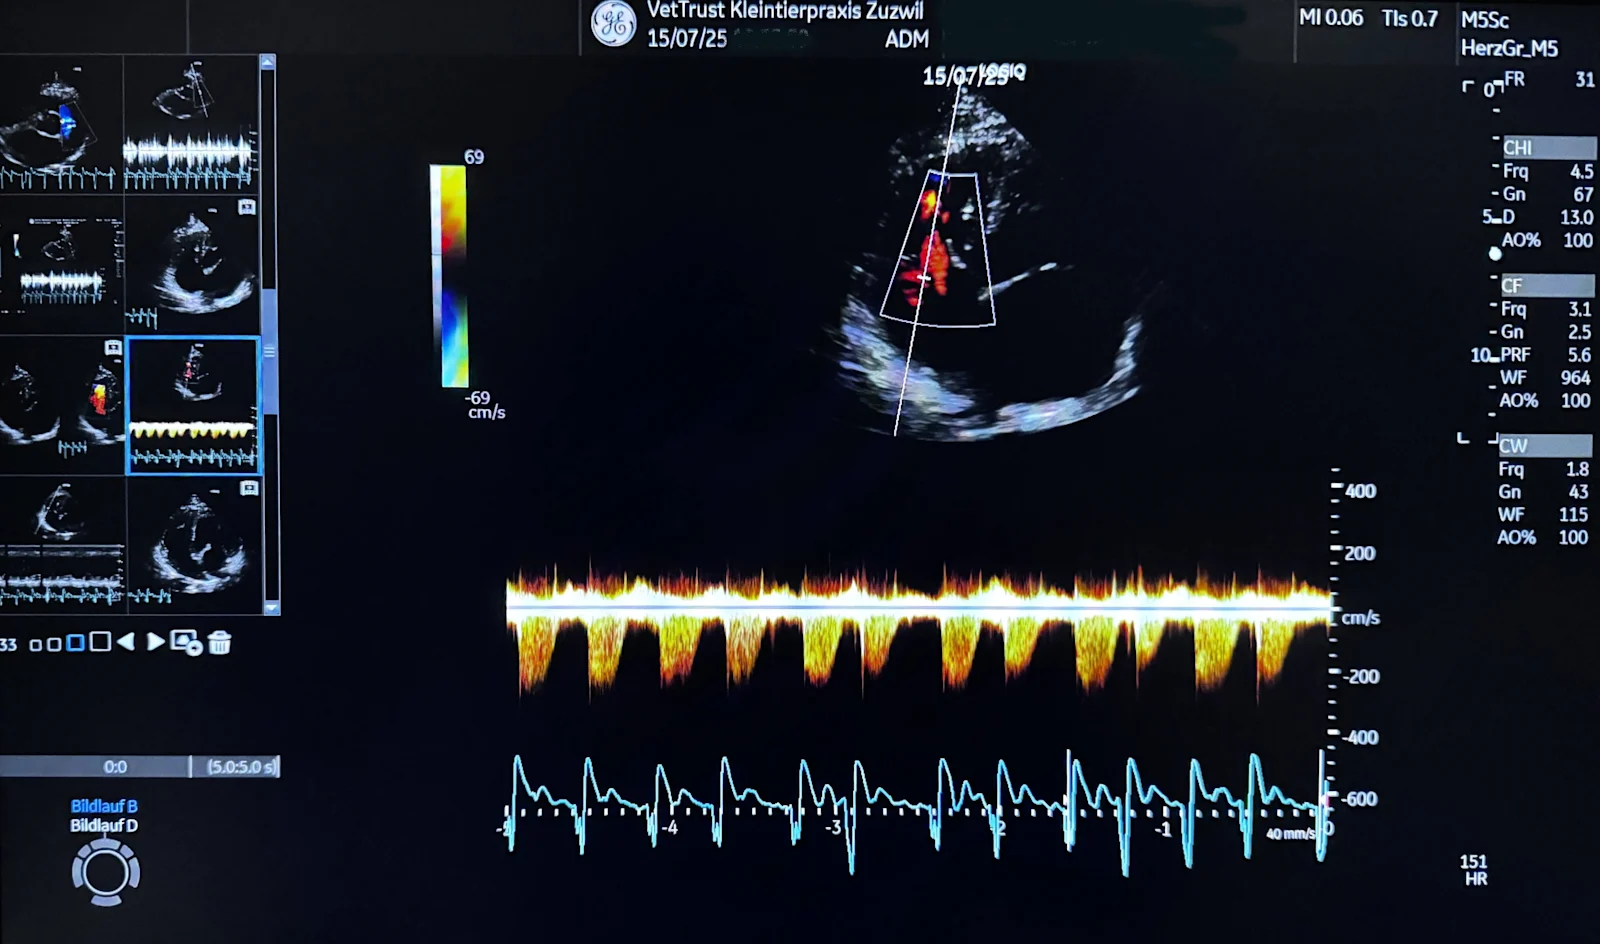

Échographie cardiaque moderne: précision et haute expertise par Dr. med. vet. Tanja Rietmann (cand. CAS Cardiology Companion Animals ESAVS, Master of Small Animal Ultrasonography, Tech)

Les systèmes standards manquent souvent de résolution ou de Doppler. Le cœur est complexe et mobile. Les micro-atteintes des valves, du myocarde et du flux exigent une image d’excellence, de la puissance de calcul, des sondes adaptées et des analyses modernes, y compris assistées par IA.

Examen doux, indolore et le plus souvent sans anesthésie, dans une salle tamisée sur un tapis matelassé. Notre équipe aide au positionnement et reste présente calmement. Environ 30 minutes. Petites zones tondues, gel appliqué, sonde sur le thorax, images en temps réel. Résultats interprétés puis expliqués.